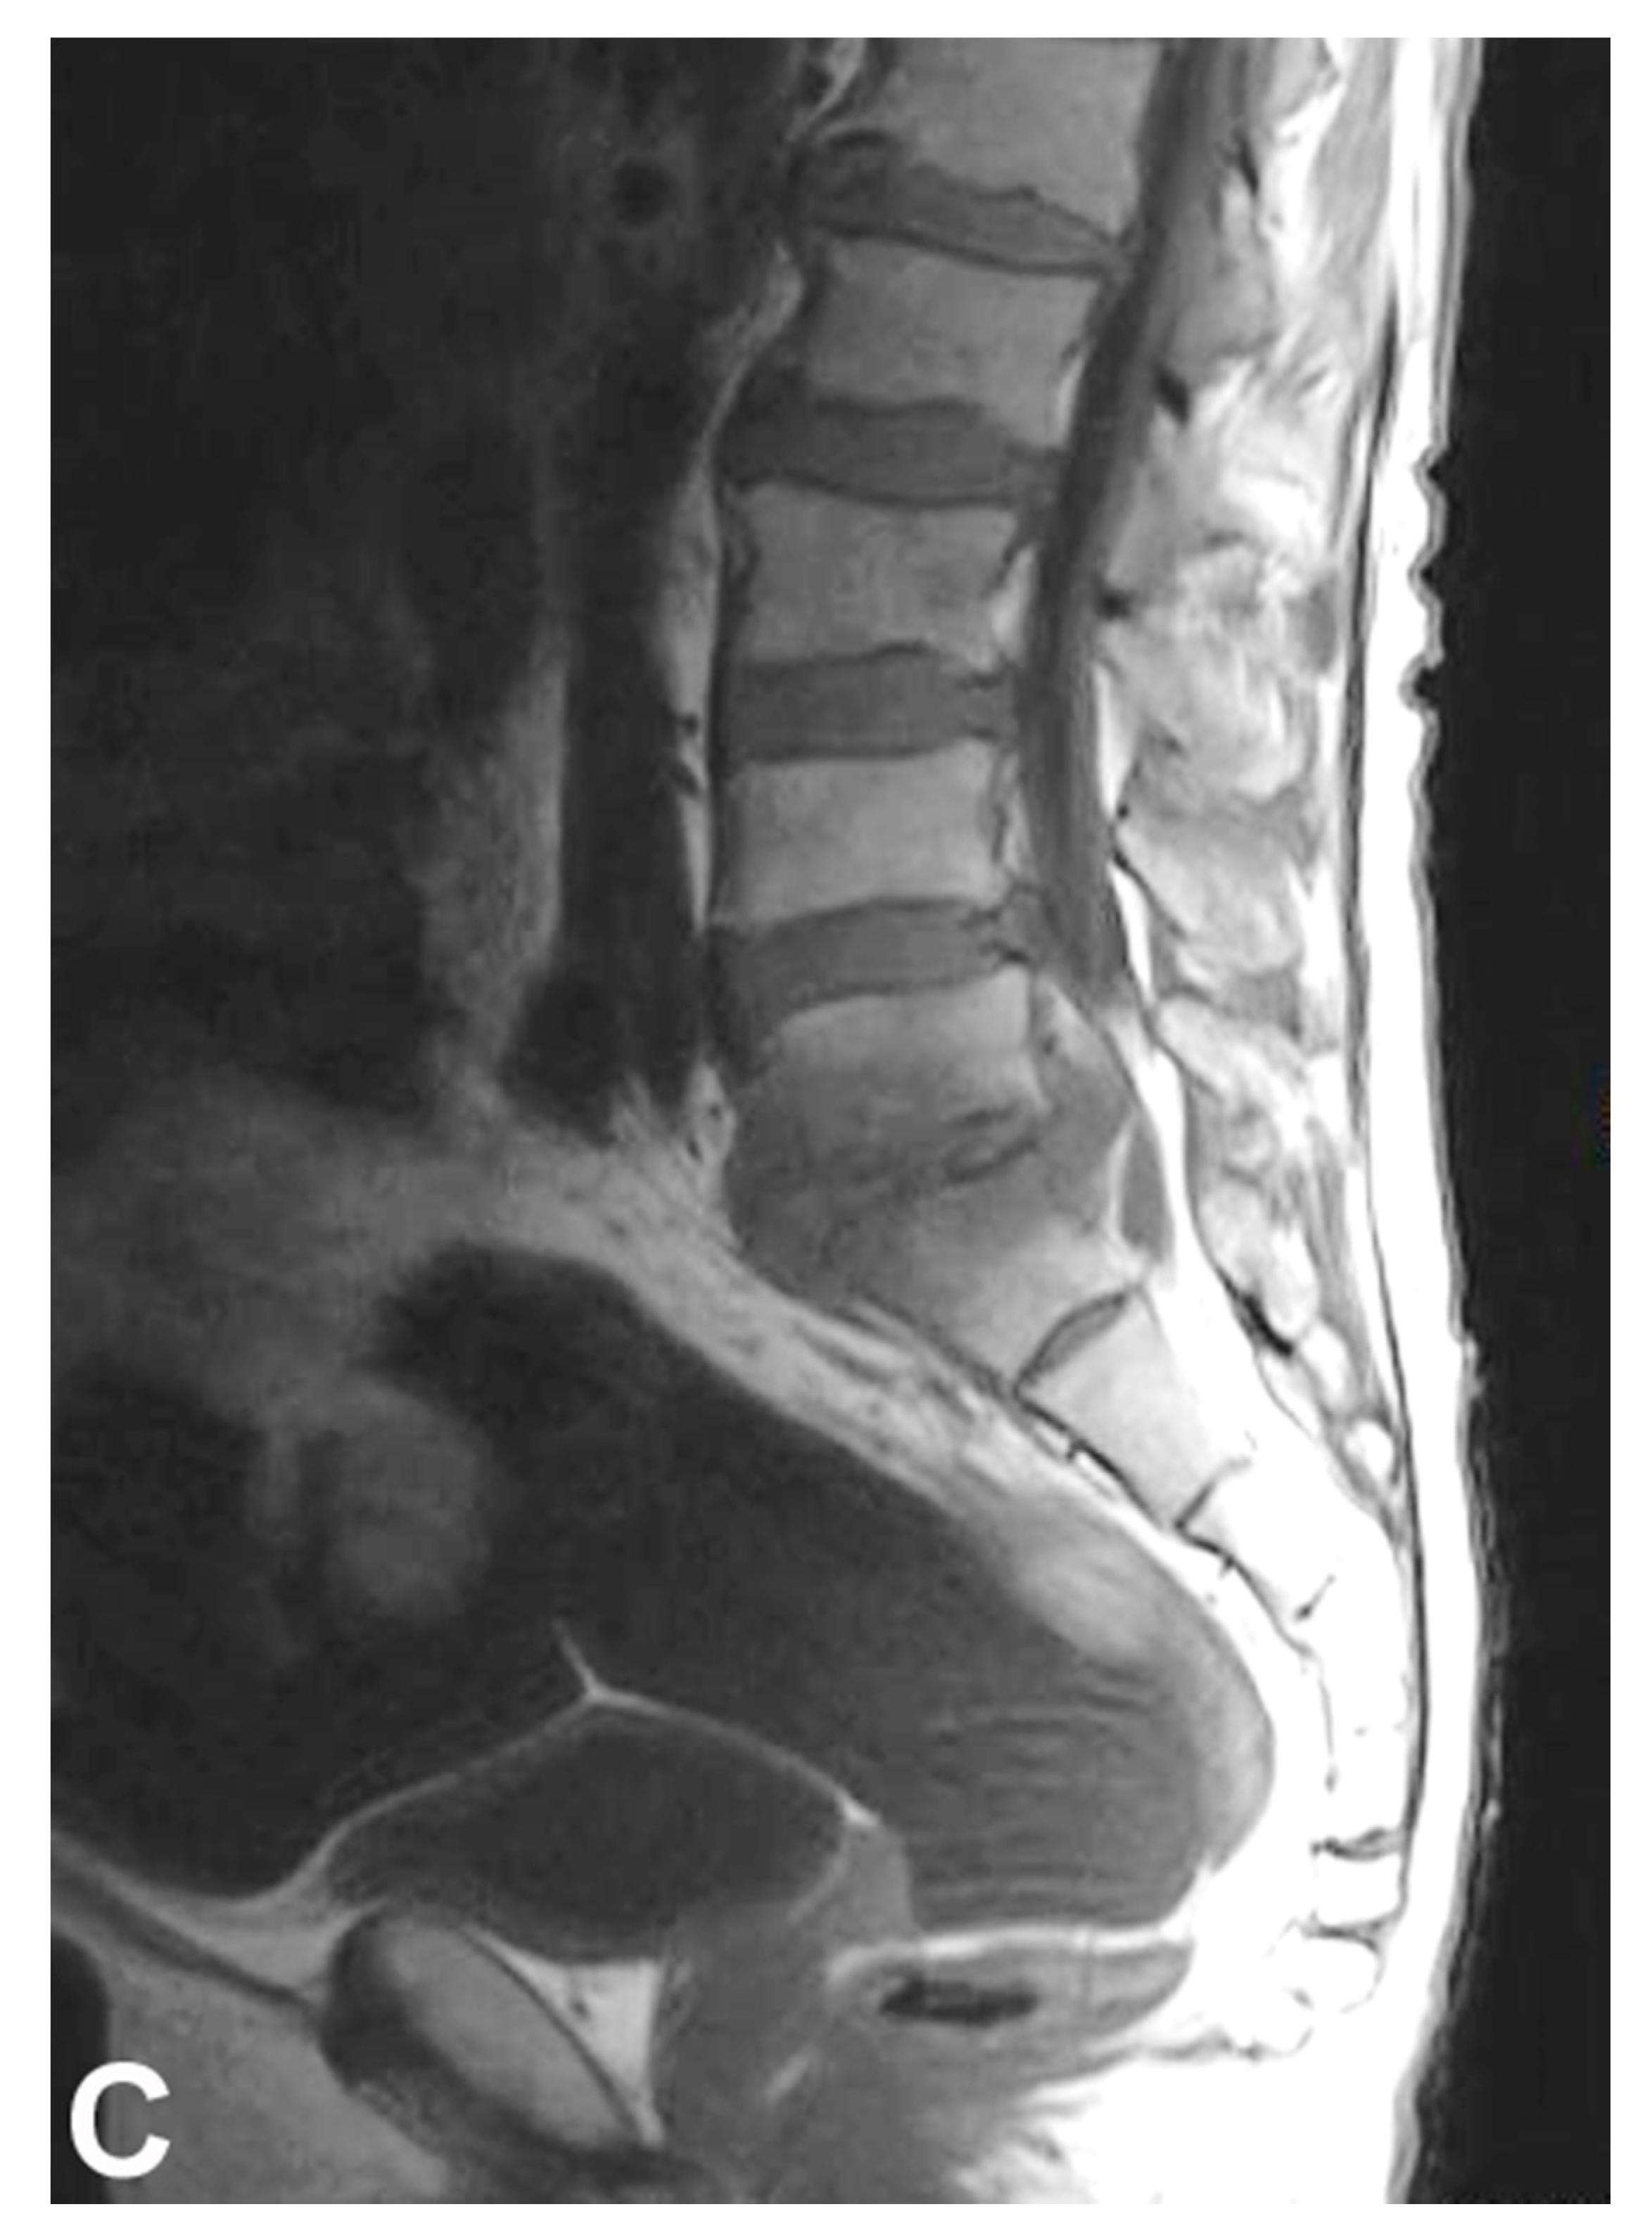

5. Diagnosis